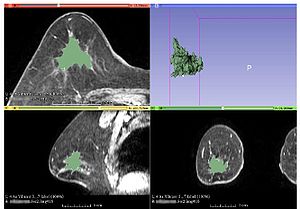

MR Diffusion-weighted Imaging-based Subcutaneous Tumour Volumetry in a Xenografted Nude Mouse Model using 3D Slicer: An Accurate and Repeatable Method

Publication: Sci Rep. 2015 Oct 22;5:15653. PMID: 26489359 | PDF Authors: Ma Z, Chen X, Huang Y, He L, Liang C, Liang C, Liu Z. Institution: Department of Radiology, Guangdong General Hospital, Guangdong Academy of Medical Sciences, Guangzhou, Guangdong, China. Background/Purpose: Accurate and repeatable measurement of the gross tumor volume(GTV) of subcutaneous xenografts is crucial in the evaluation of anti-tumor therapy. Formula and image-based manual segmentation methods are commonly used for GTV measurement but are hindered by low accuracy and reproducibility. 3D Slicer is open-source software that provides semiautomatic segmentation for GTV measurements. In our study, subcutaneous GTVs from nude mouse xenografts were measured by semiautomatic segmentation with 3D Slicer based on morphological magnetic resonance imaging(mMRI) or diffusion-weighted imaging(DWI)(b = 0,20,800 s/mm(2)) . These GTVs were then compared with those obtained via the formula and image-based manual segmentation methods with ITK software using the true tumor volume as the standard reference. The effects of tumor size and shape on GTVs measurements were also investigated. Our results showed that, when compared with the true tumor volume, segmentation for DWI(P = 0.060-0.671) resulted in better accuracy than that mMRI(P < 0.001) and the formula method(P < 0.001). Furthermore, semiautomatic segmentation for DWI(intraclass correlation coefficient, ICC = 0.9999) resulted in higher reliability than manual segmentation(ICC = 0.9996-0.9998). Tumour size and shape had no effects on GTV measurement across all methods. Therefore, DWI-based semiautomatic segmentation, which is accurate and reproducible and also provides biological information, is the optimal GTV measurement method in the assessment of anti-tumor treatments. Funding:

|

MRI-based tumor volume segmentations with the semiautomatic and manual segmentation methods. Tumour segmentation was performed with 3D Slicer v4.3 software. The leftmost images present the same subcutaneous tumor (red arrows) on an axial slice: b = 0 s/mm2 DWI (uppermost), b = 20 s/mm2 DWI (second image from the top), b = 800 s/mm2 DWI (third image from the top), and mMRI MRI (lowest). Moreover, comparison of total tumors in corresponding sequences obtained from semiautomatic segmentation by 3D Slicer (green, middle images) and manual segmentation by ITK (blue, rightmost images) are presented. |